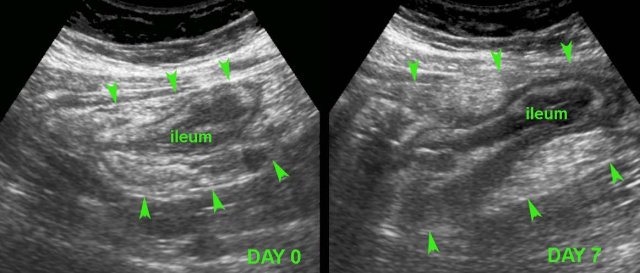

In this young patient, USfindings were compatible with both early Crohn’s ileitis and right-sided infectious ileocolitis.

Repeated US after 7 days waspathognomonic for Crohn’s disease.

Note that both wall thickening and surrounding inflamed fat have markedly increased in volume (arrowheads).